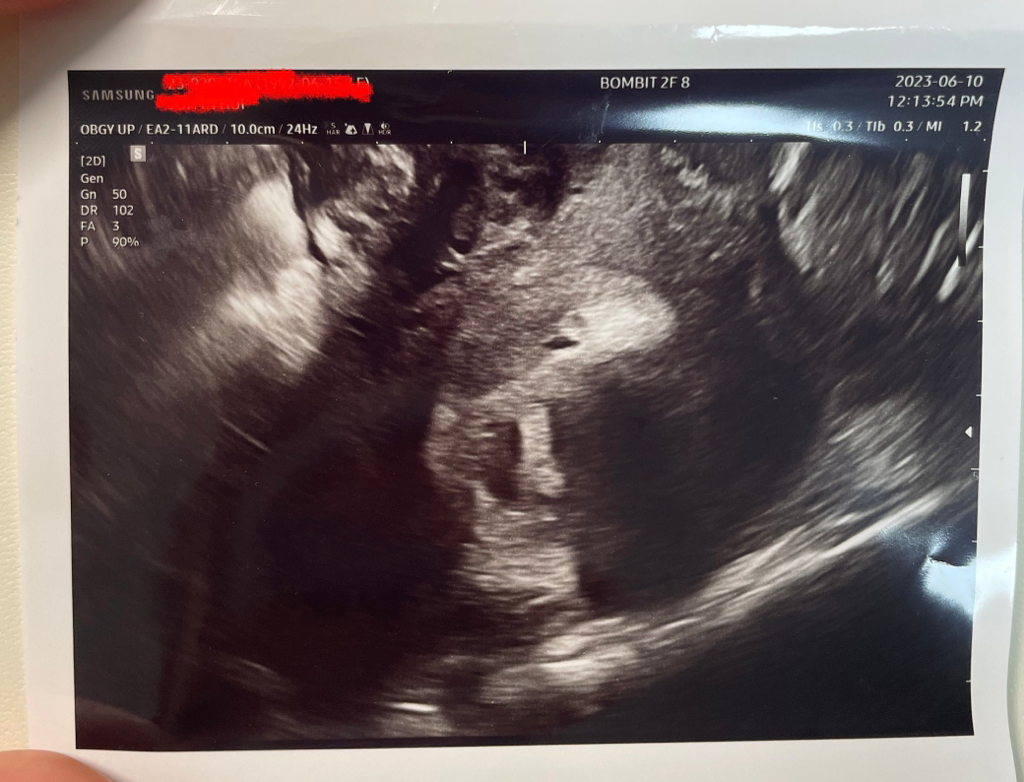

• 3번 째 사진

올려주신 초음파 사진은 아기집을 찍은 사진이라 자궁근종은 명확하지 않습니다.